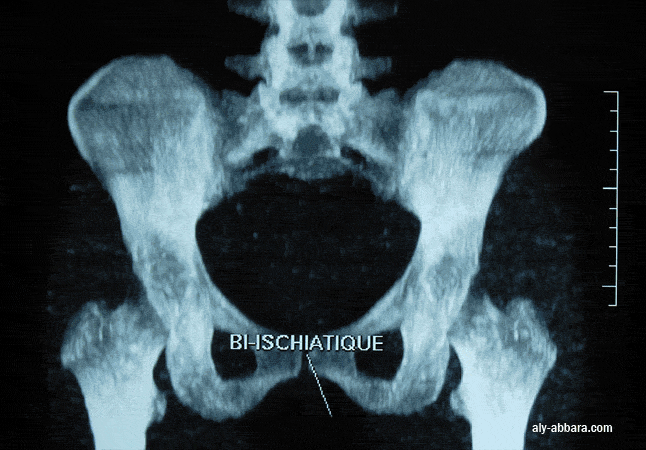

Bassin féminin vu de face : mesure du diamètre bi-ischiatique : la distance mesurée entre

les faces internes des deux tubérosités ischiatiques ; en moyenne 110 mm.